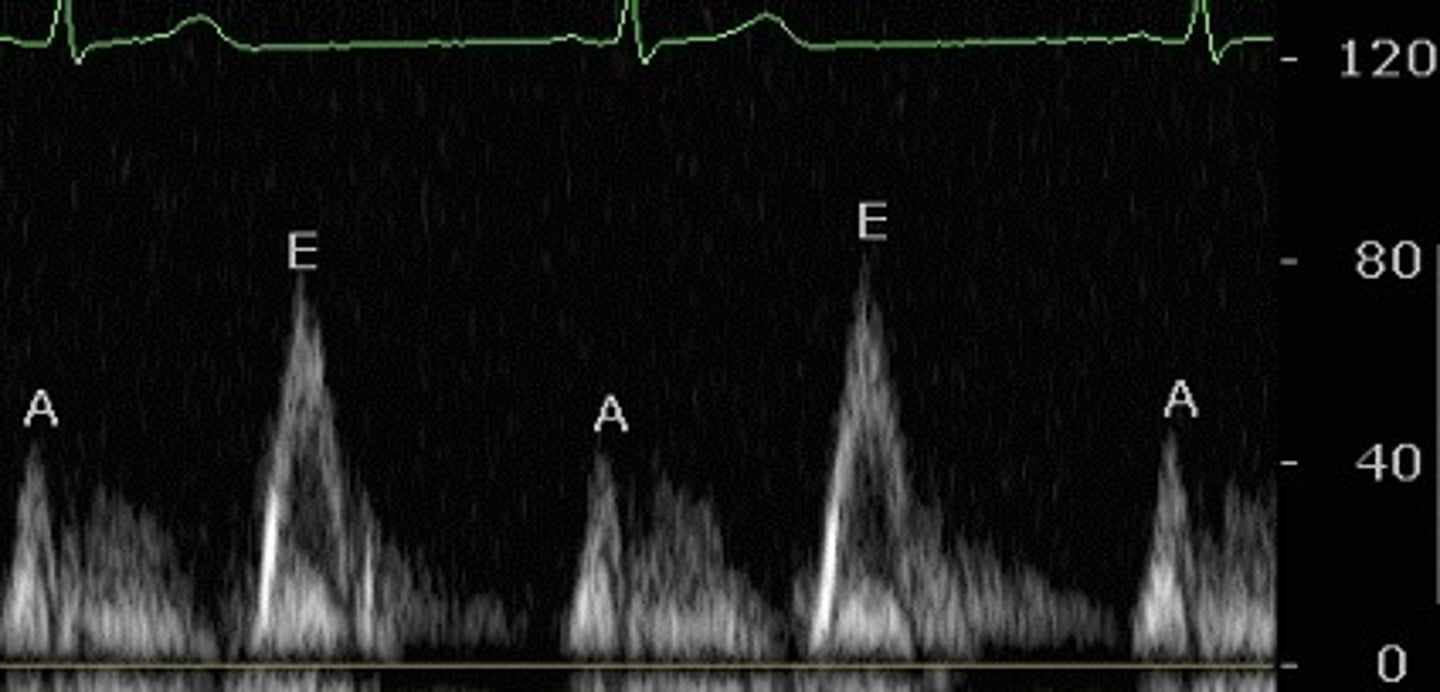

early diastolic filling, near the end of the T wave

what does the E wave indicate on pulsed wave Doppler? What EKG feature does it correspond with?

flow from atrium to ventricle during atrial contraction (atrial kick), just after P wave

what does the A wave indicate on pulsed wave Doppler? What EKG feature does it correspond with?

pulsed wave doppler, the peaks are hollow

which type of quantitative doppler is this? How can you tell?